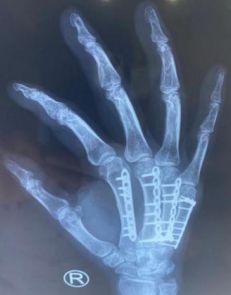

熊医生位患者安排CT检查,见2-5掌骨骨折。“医生,严重吗?”,“你这个属于多发性掌骨骨折,手法复位后,小夹板固定一般达不到满意效果。可以选择切开复位,用克氏针或者钢板内固定。钢板比克氏针固定的更加牢靠,而且不容易为内固定物松动断裂。内固定的优点很多,第一,没有钉道感染的风险;第二,内固定更牢固,不容易移位;第三,术后日常生活很方便,可以在早期进行手部功能的锻炼。”熊医生耐心地为患者解答疑问。

最终,患者选择了钢板内固定的手术方式。完善各项术前准备工作,熊医师手术团队为患者进行了右2-5掌骨骨折切开复位内固定术,术中手法复位骨折断端,观察对位良好,使用钢板内固定,手术顺利。术后,医护团队在护理上指导患者注意患肢休息,加强功能锻炼,局部热敷促进血液循环,同时饮食清淡,多喝牛奶和吃新鲜水果,促进钙质的吸收,患者恢复良好。

2021年8月,患者术后一年来院复查时,其手指伸并、拳头张握活动非常灵活,手的功能和力量恢复都非常好。